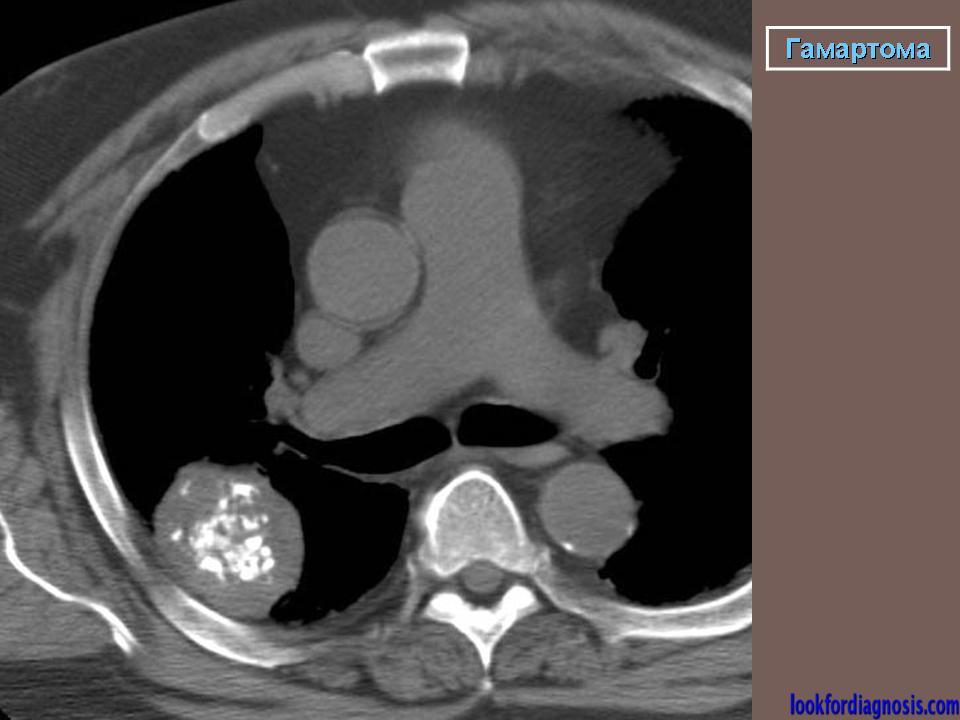

Гамартома

Приложения:

1.gpm_.2_582.jpg2.gam_.3_505.jpg3._gam.4_406.jpg